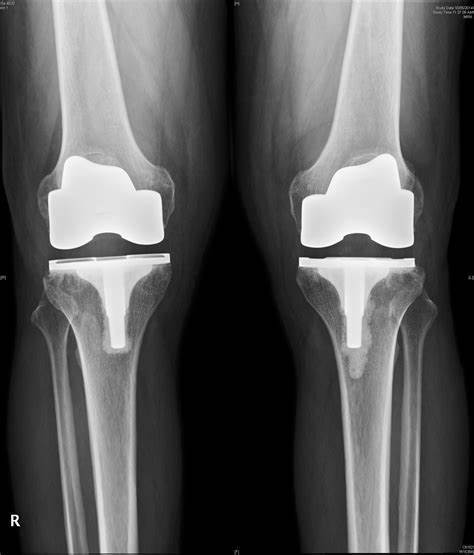

那么如何才能帮助患者解决这个问题呢?膝关节置换手术就被发明出来了。既然这些疾病导致患者的关节软骨被侵蚀掉了,关节变得狭窄,那么想办法把严重增生的骨贅切除,已经被磨损殆尽的关节换成跟原来一样的光滑的关节就好了!这就有点像是我们给牙换牙套,是一个过程。大家看下图就会明白这个过程了。

图片

大家看下面这个动图,可能会觉得这个手术非常的简单,但这是模拟的动图,实际的手术操作非常复杂,要在膝关节的前方切一个纵行的切口,逐层的切开皮肤、皮下脂肪、筋膜、肌肉,进入关节囊,这个创伤是比较大的。之后要将影响关节功能比较多的骨赘,也就是骨质增生切除掉,再使用专用的模具逐渐修整关节的表面,最后替换上假体,之后等待假体固定坚固以后,反复的清洗关节腔,再逐层的将切口缝上。

这样一个手术过程,手术非常熟练的专家,换假体的过程需要20~40分钟左右,而切开再缝合的过程可能要一个小时。